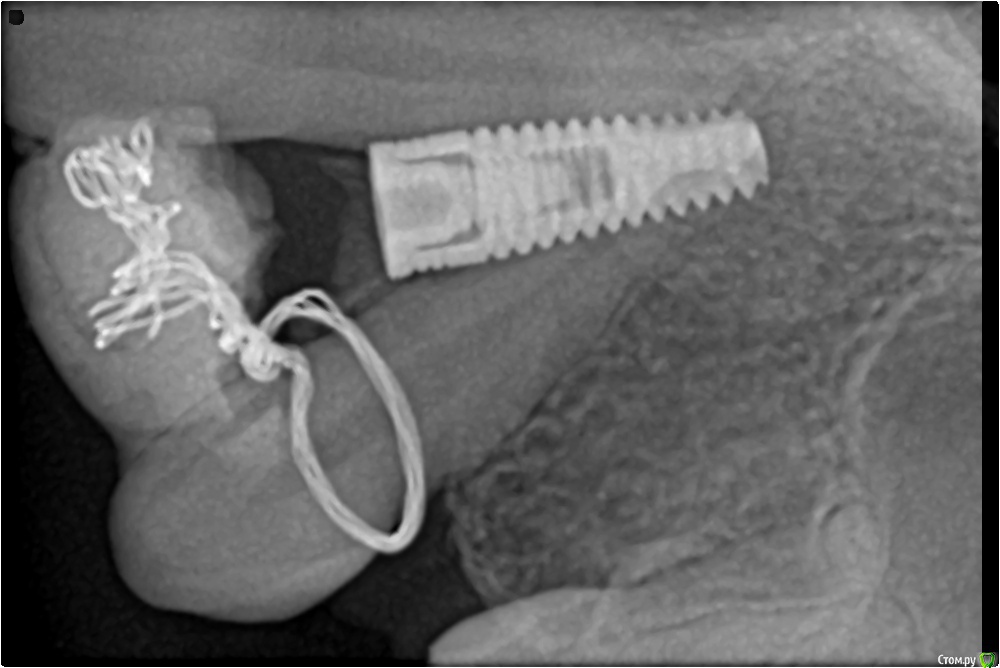

demida Опубликовано 5 мая, 2015 Поделиться Опубликовано 5 мая, 2015 хочу попросить Вас посмотреть мои снимки. У меня с детства не было двойки, клык тройку врачи перетащили скобами на место (изначально он занимал место двойки), поэтому корень зуба получился немного наклоненный. На место него мне вживили имлпант, первый раз имплант не прижился, выпал. После мне укрепили кость и вставили повторно. Но когда пришла делать снимок увидела то, что имплант близко расположен к корню. Врач сказал что причин для беспокойства нет, и что корень находится в другой плоскости и возможно просто снимок так искажает. А реакцию зуба (в частности единички) на холодное и небольшую боль при нажатие аргументирует тем, что корень и имплант близко находится друг другу. Иногда чувствую пульсирующую боль при нагрузке и небольшое покраснение хоть,но прошло 2 недели после операции. Консультировалась у другого врача, он говорит, что если бы мне задели корень зуба у меня бы была ужасная боль не только при нажатии, температура, кровотечение и т.д. Я молодая девушка и не хочу потерять еще один зуб, посоветуйте что мне нужно сделать и как понять нормально ли данные ощущения. Ссылка на комментарий